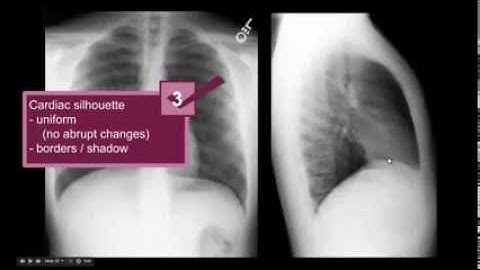

Lateral CXR Part 1 Anatomy - "EM in 5"